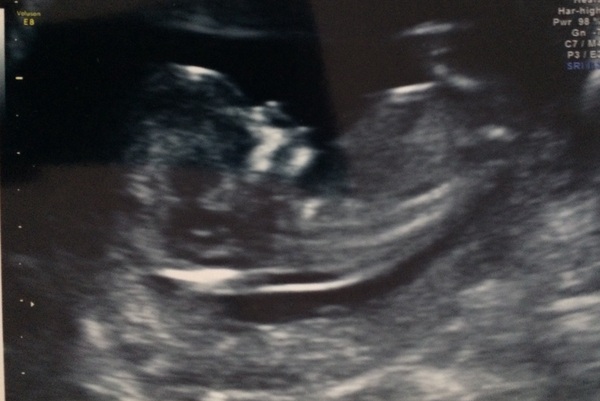

I had my dating scan this afternoon & everything looks fine. I was so anxious, much more so than I was with DD.

They have now put my EDD at 31/03/2017

Congrats little spoon , amazing to see little ones. My due date is 30/03/17 - hope it's earlier tho as still got sickness and keep spitting! Hope everyone with headaches and nausea get well soon X

What a lot of beautiful scans :)

Hi everyone - seems there are a lot of us still feeling rubbish! But lots of lovely scan pics.

At the mo we just laugh it off as we haven't told family yet (10 weeks today, not sure what I am waiting for!!) I think once we have a scan pic we will tell her, as my stomachs is showing now. Good luck with your scan today.

We told DD, who is five, last week. She knows I've had a 'poorly tummy' for weeks and was getting worried. I figured at 10w with a good scan I was probably as safe as it gets at this stage. We showed her the scan picture, (is that me when I was in your tummy? Is that DS when he was in your tummy?) she was very excited - she's really wanted another sibling ('one that doesn't have to die') for ages.